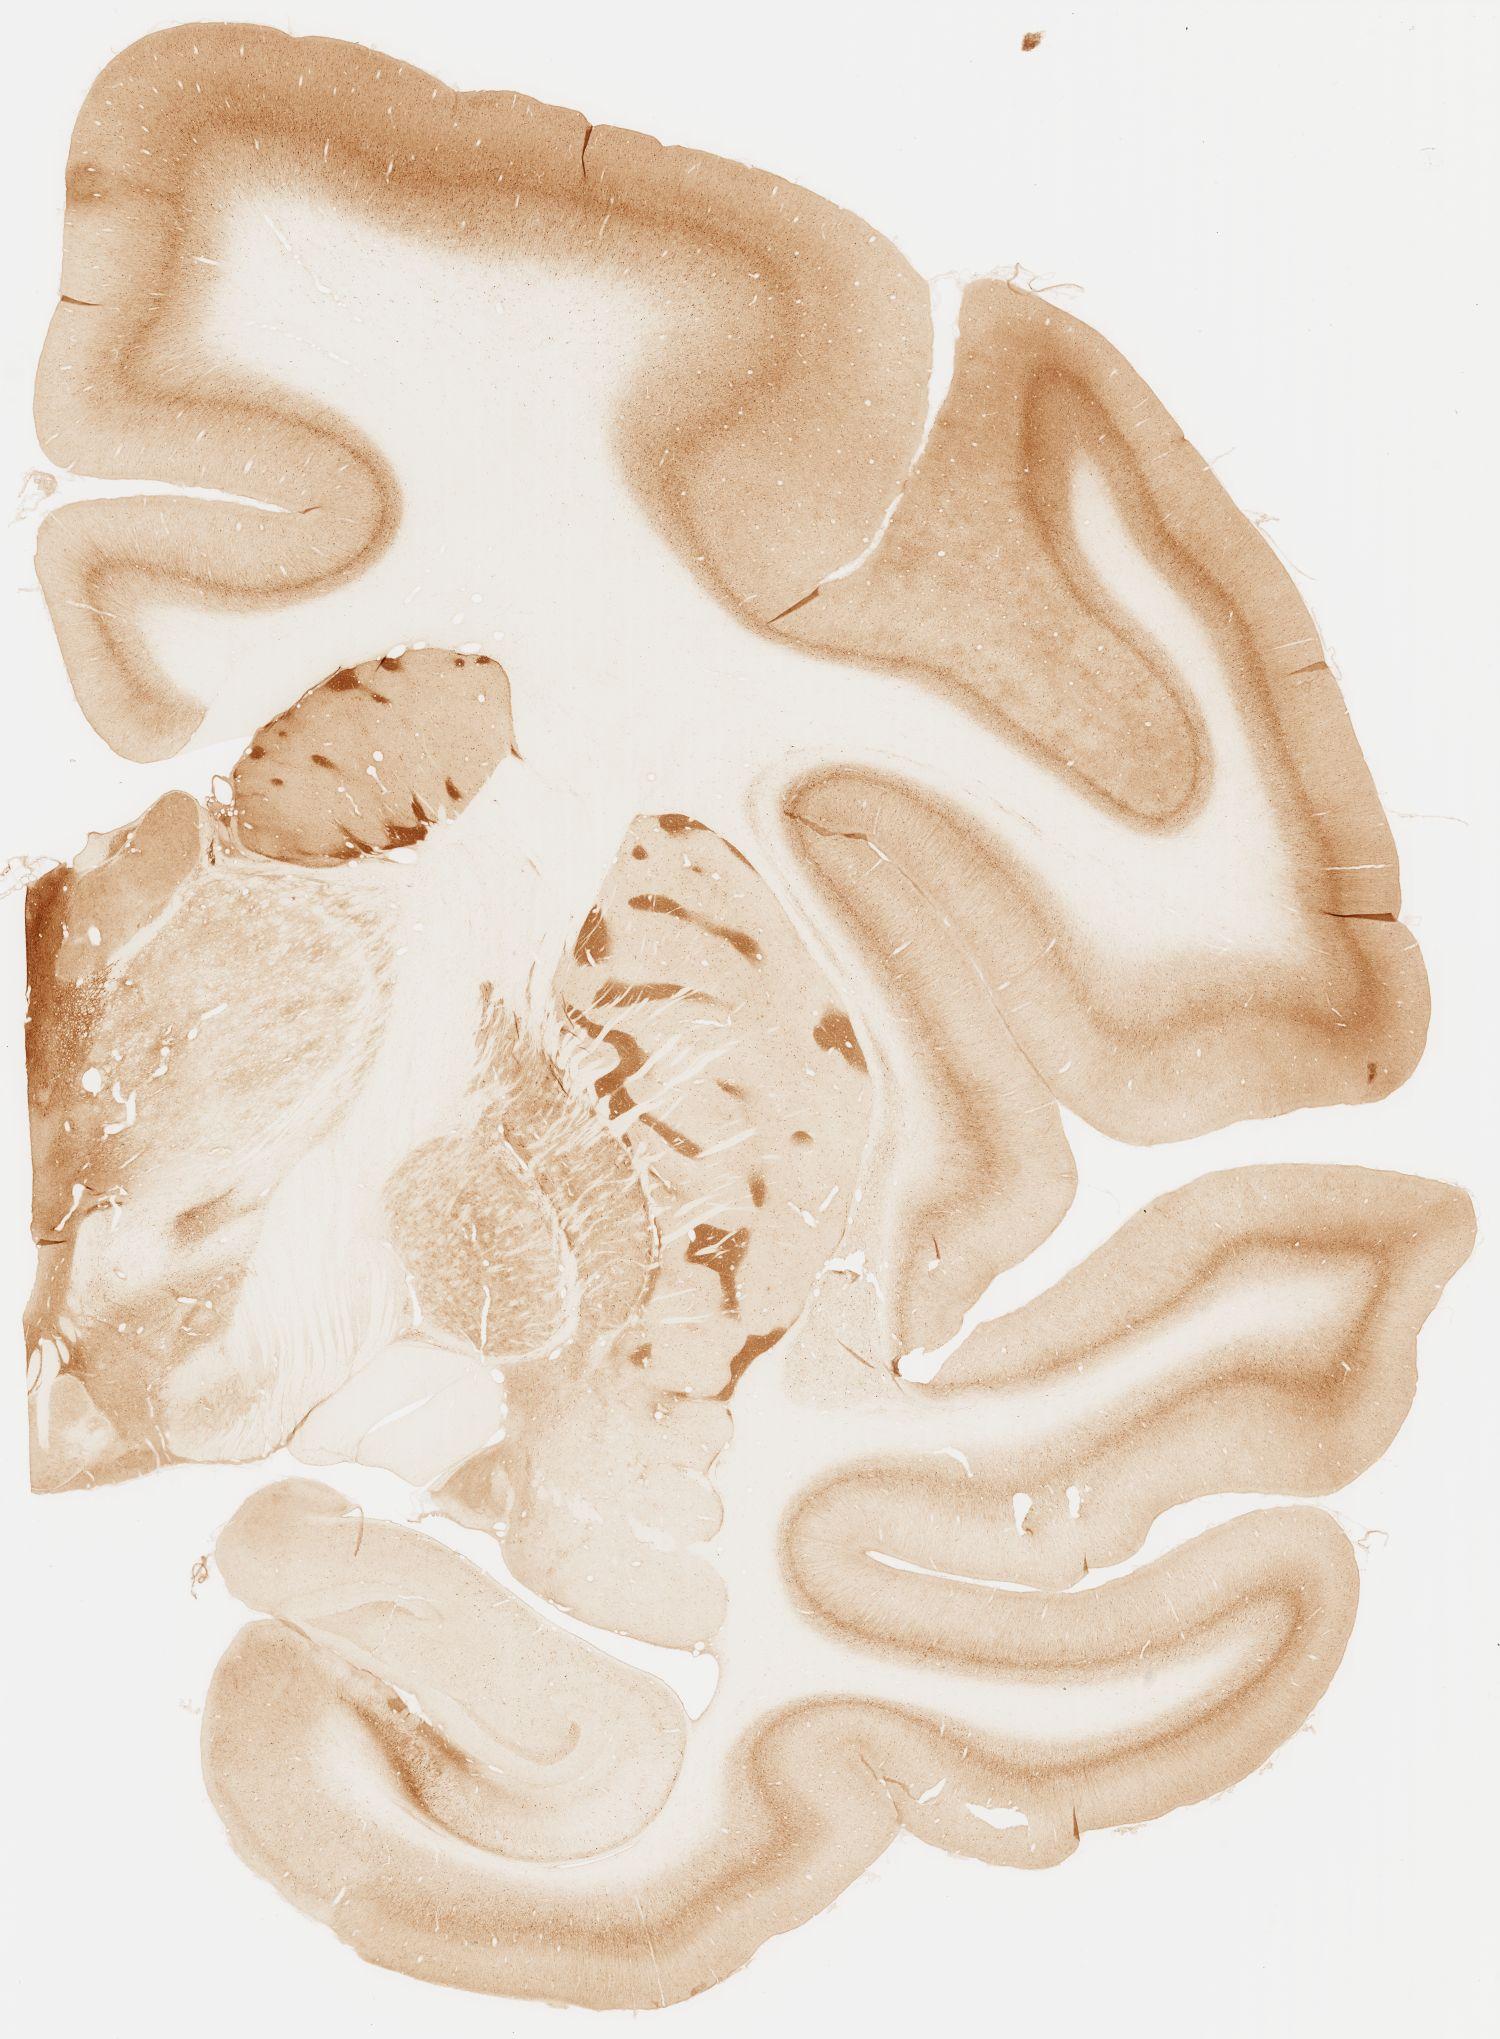

Datasets -> Macaca Fascicularis -> KChIP1, (Potassium Voltage-Gated Channel-Interacting Protein 1), coronal, immuno, Whole-Brain, adult

[ Metadata ]   ·   Source: Edward G. Jones

Displaying Sections 81 thru 92 of 92 Sections for this Dataset